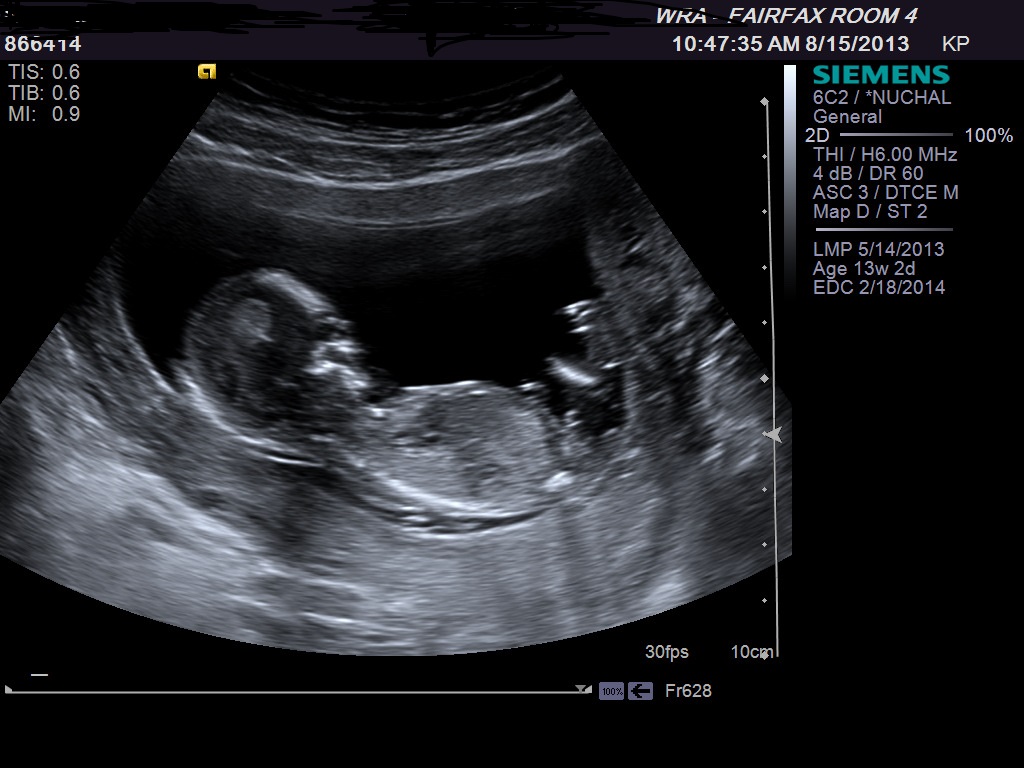

I have to go to library to post my ultrasound, and I cant wait till my nex appt Oct to know if its a boy or Girl. Please Can you guess from ultrasound i am oposting hereAttachment 13979Attachment 13980Attachment 13981